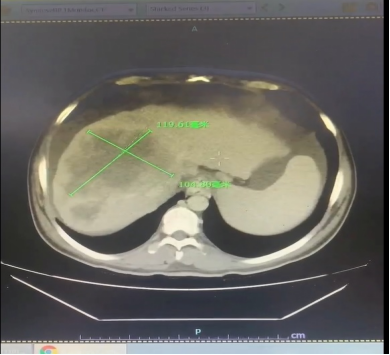

省肿瘤医院CT图像:

2023.10.19复查肝脏CT提示:肝脏左右叶比例失调,肝裂增宽,肝S4段见巨大实性不规则团块状低密度影,最大截面约9.3*7.2cm,增强后无明显强化,其周围并伴相似性质结节影,肝动脉左侧枝及门静脉左侧枝受压,右动脉S8段分支、门静脉右前段分支及肝中静脉显示不明显,脾大,密度均匀,未见异常强化,脾脏周围及食管静脉曲张